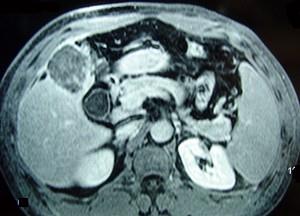

问题 男性,60岁,右上腹胀不适,右肝区叩击痛,影像检查如图,最可能的诊断是 ( )

选项 A、肝硬化、膈下脓肿 B、肝硬化、结节性增生 C、肝硬化、再生性肝癌 D、肝硬化、腹腔间质瘤 E、肝硬化

答案 C